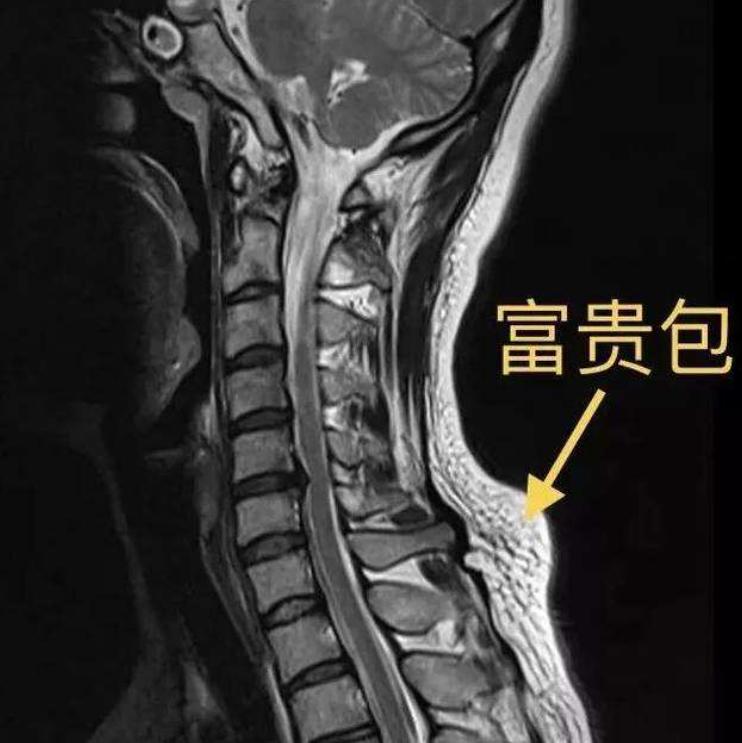

它的出现主要是因为颈椎与胸椎连接部分出现了"后凸"——通常,人的颈椎会有一个正常的生理曲度,但如果人处于长时间低头、保持不良站姿/坐姿,或者受到外伤(比如椎体的压缩骨折)等等因素影响时,颈椎的曲度就会出现异常变化,即后凸角度增大,最终使得"富贵包"出现在颈椎与胸椎连接的区域,见下图。